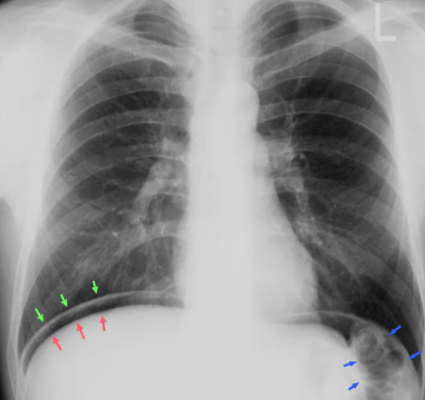

The red arrows indicate the upper border of the (BLANK).

B) Liver

To what structure are the arrows pointing?

A) Intestinal walls

B) Inner and outer layers of the intestine